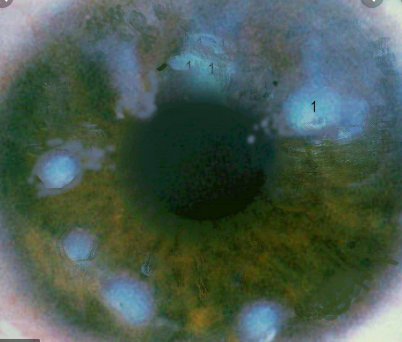

Salzmann’s Nodular Degeneration